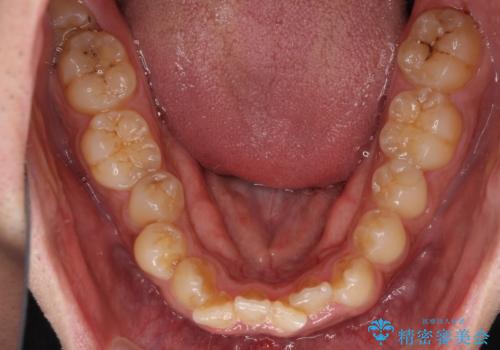

- 前歯のデコボコを気にして来院された患者様です。

前歯が90度近く捻れていたため、しっかりと治すことを考えるとワイヤー矯正の方がおすすめではありましたが、本人の希望によりインビザラインを用いて矯正治療を行うこととしました。

インビザラインは、十分な装着時間が達成されると前歯のデコボコをしっかりと改善できますが、1日の装着時間が20時間に達しなくなると、不十分な仕上がりとなるため、しっかりと装着するよう指示をしました。

途中2年強の来院がなく、改善されていたデコボコが元に戻ったり、装着時間が不足しており前歯のデコボコは十分に改善することはできませんでしたが、5年間の有効期限内で可能な限り歯列を整えることができました。